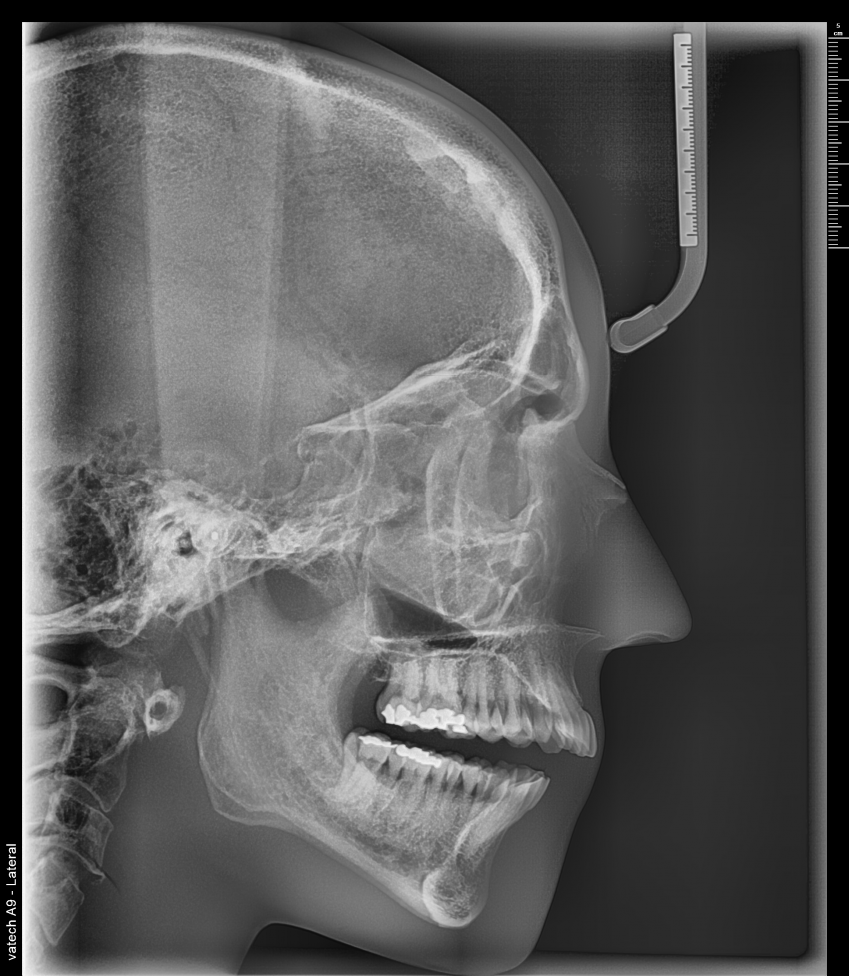

A9 cuenta con una tecnología lite que además de la función PANO + CEPH te permite obtener imágenes CT de manera lite para tu diagnóstico. Proporciona las imágenes más precisas y de mayor calidad.

Las imágenes 3D permiten realizar diagnósticos precisos para planificar los tratamientos dentales. Incluye la áreas maxilar y mandibular en una sola exposición. Ideal para cirugías de implantes y diagnósticos en cirugía oral.